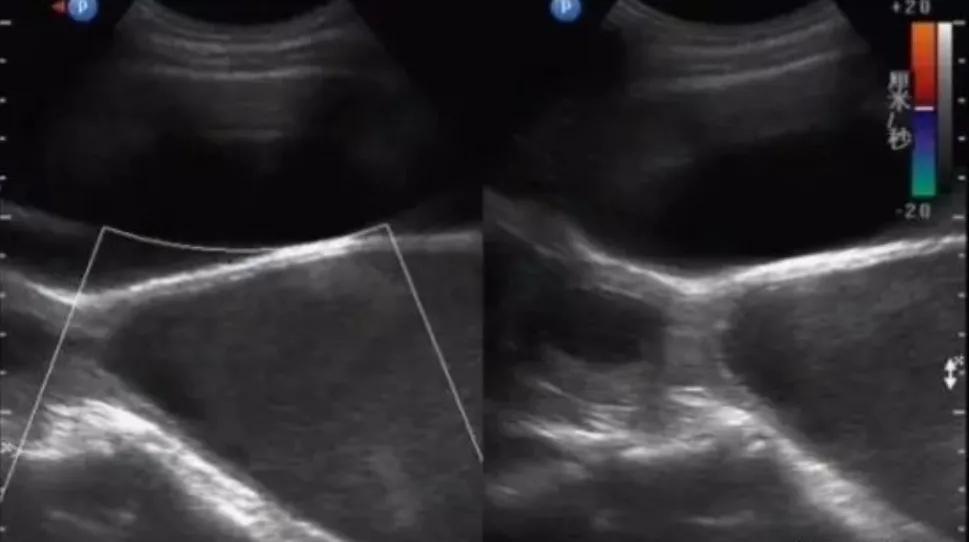

B超下阴道瓣闭锁

第二种是闭锁型:也就是完全封闭状态,这是不正常现象,因为女性青春期后子宫壁就会每月脱落一次,与此同时卵巢会排出一颗卵子,只是生理结构还未发育成熟尚不能妊娠。阴道瓣锁闭后会引发许多问题,容易引起阴道、子宫、输卵管积血发生炎症。发病率大约1/1000~1/2000,处女膜闭锁可合并其他女性生殖系统发育畸形及其他泌尿系统发病的风险,如阴道纵隔、双子宫、单侧肾缺如等。因此青春期后未来潮一定要及时去医院检查。